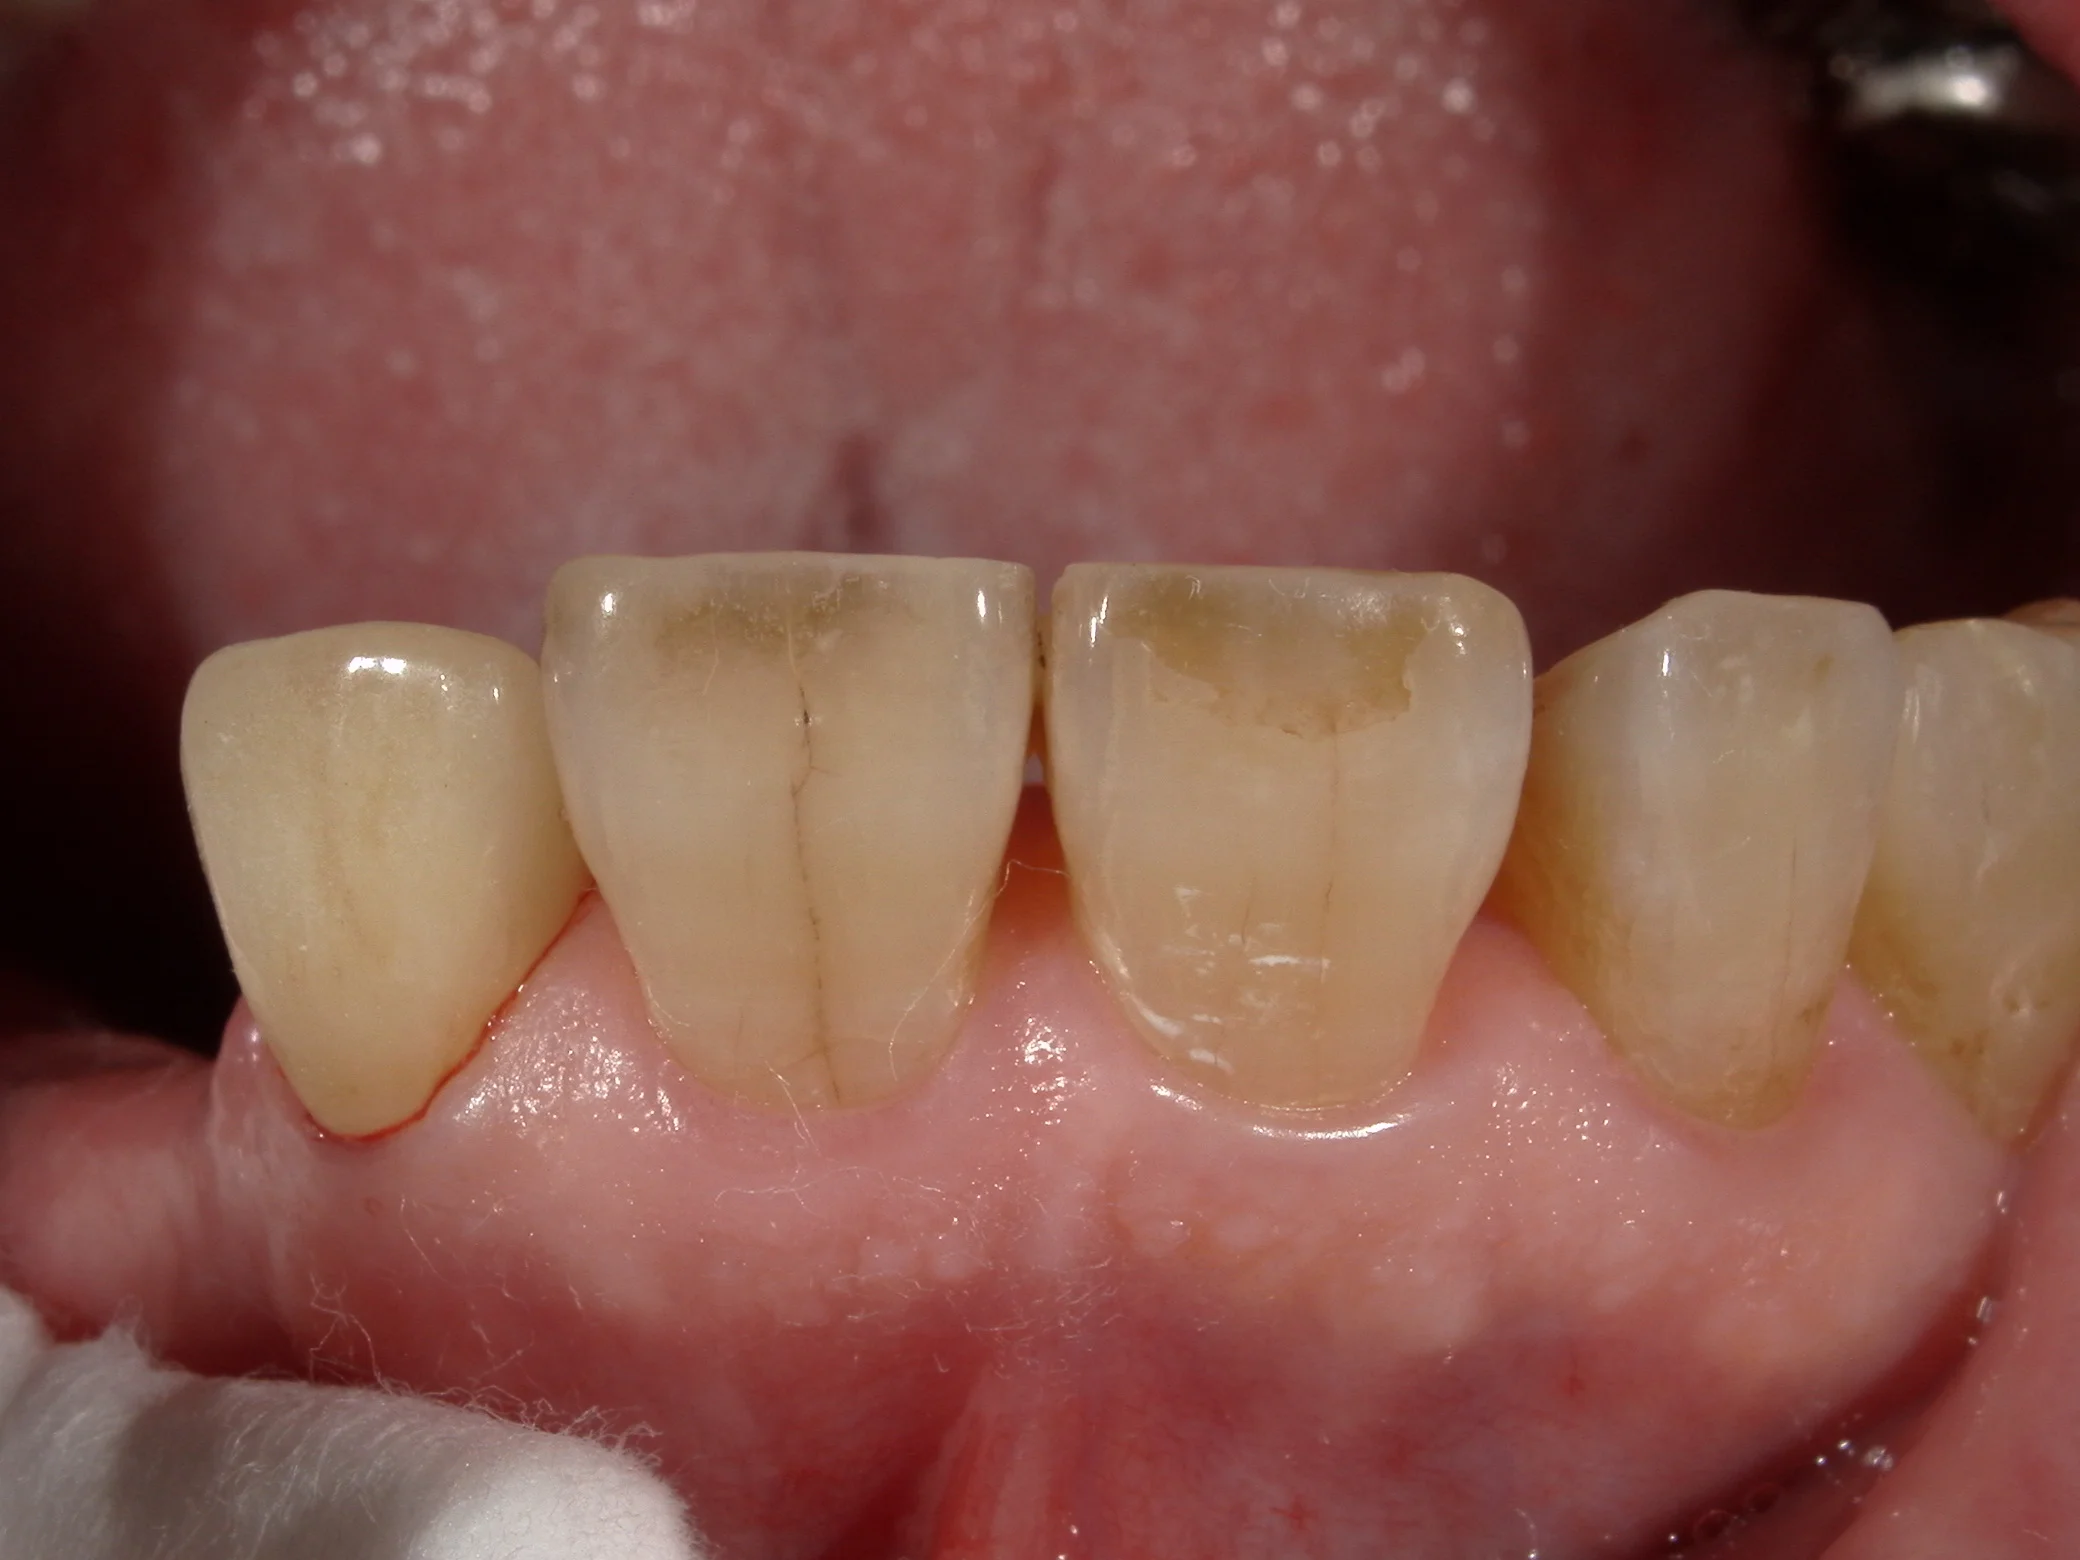

そして、上記のカメラを使用して作成したセラミックがこちらです。

血液の痕で分かりやすいですが、画面の左側がセラミックです。